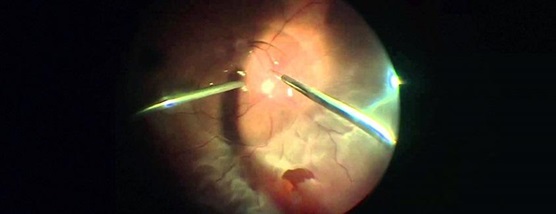

Витрэктомия (вид со стороны хирурга)

И самое интересное то, что картинка, которую видит хирург получается в перевернутом «вверх ногами» виде и реально не существует – это мнимое изображение, висящее между глазом и системой линз. Поэтому витреоретинальные хирурги учатся видеть такие образы и фокусироваться на них, а для «переворота» изображения существуют система инвертирования, которая подключается по запросу.

В некоторых случаях при работе удобнее работать с прямыми контактными линзами, установленными прямо на поверхность роговицы, например при работе в центральных областях роговицы – тогда изображение получается прямым и истинным.

Работа через контактную линзу